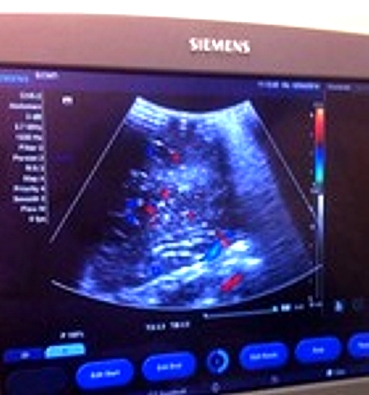

Врачом ультразвуковой диагностики Венерой Якубовой и бригадой нейрохирургов БСМП впервые во врачебной практике Набережных Челнов была выполнена интраоперационная ультразвуковая нейронавигация новообразования головного мозга в 3D-режиме.

54-летний пациент поступил в БСМП с подозрением на инсульт. После обследования ему был поставлен диагноз: фибриллярная астроцитома левой лобной доли головного мозга малых размеров. Современные технологии визуализации опухолей позволили определить точную локализацию новообразования и совершить радикальное ее иссечение с минимальным повреждением ткани головного мозга, сообщает пресс-служба Минздрава РТ.